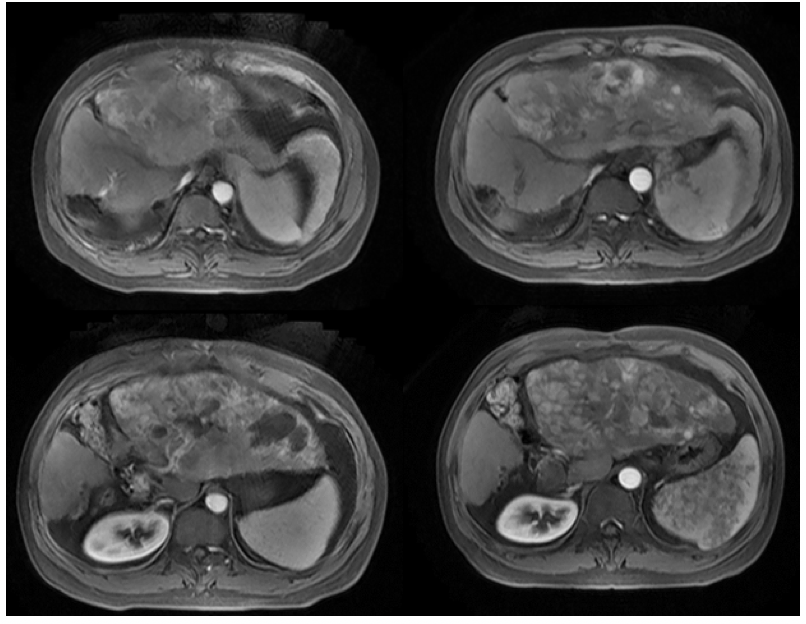

2021年9月7日MR提示,肝癌综合治疗后,病灶活动,大小约18.2cm×12.2cm,门静脉左支癌栓;肝门区淋巴结显示;肝硬化,腹水(图2)。

图2. 2021年9月7日复查MR

复查评估显示,肝内病灶较前稍增大,肿瘤标记物较前升高,mRECIST标准:疾病进展(PD)(图3)。

图3. MR复查评估